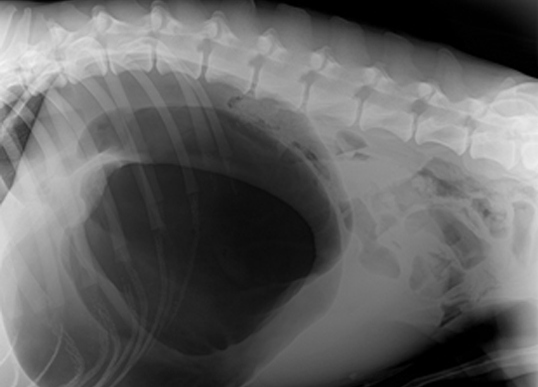

주요 질환 교상, 교통사고, 위확장염전, 자궁축농증, 디스크질환, 요도결석